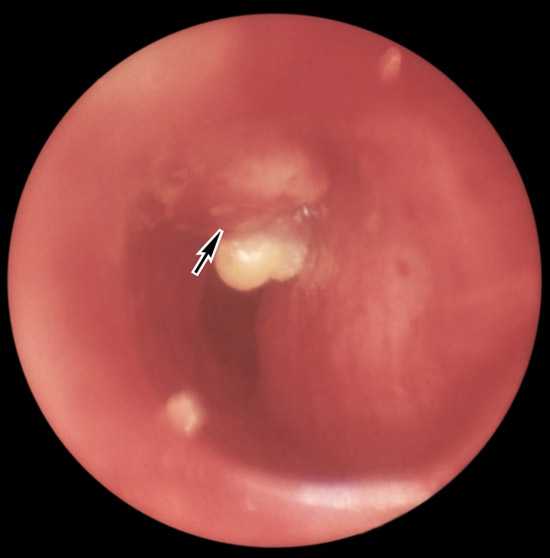

Π ΠΈΡ. 3. Π―Π·Π²Π΅Π½Π½ΡΠΉ ΡΡΠ±Π΅ΡΠΊΡΠ»Π΅Π· ΠΏΡΠ°Π²ΠΎΠ³ΠΎ Π³Π»Π°Π²Π½ΠΎΠ³ΠΎ Π±ΡΠΎΠ½Ρ Π°, ΠΊΠΎΡΠΎΡΡΠΉ ΡΠ°Π·Π²ΠΈΠ»ΡΡ Π²ΡΠ»Π΅Π΄ΡΡΠ²ΠΈΠ΅ ΠΏΡΠΎΡΡΠ²Π° Π² Π±ΡΠΎΠ½Ρ ΠΊΠ°Π·Π΅ΠΎΠ·Π½ΡΡ ΠΌΠ°ΡΡ ΠΈΠ· ΠΏΠΎΡΠ°ΠΆΠ΅Π½Π½ΡΡ Π²Π½ΡΡΡΠΈΠ³ΡΡΠ΄Π½ΡΡ Π»ΠΈΠΌΡΠ°ΡΠΈΡΠ΅ΡΠΊΠΈΡ ΡΠ·Π»ΠΎΠ² (ΡΠ²ΠΈΡΠ΅Π²ΠΎΠ΅ ΠΎΡΠ²Π΅ΡΡΡΠΈΠ΅ ΡΠΊΠ°Π·Π°Π½ΠΎ ΡΡΡΠ΅Π»ΠΊΠΎΠΉ).

ΠΊ ΡΠΎΠ΄Π΅ΡΠΆΠ°Π½ΠΈΡ βΠΡΠΈΠ·Π½Π°ΠΊΠΈ ΠΈ ΡΠΈΠΌΠΏΡΠΎΠΌΡ ΡΡΠ±Π΅ΡΠΊΡΠ»Π΅Π·Π½ΠΎΠ³ΠΎ ΠΏΠ»Π΅Π²ΡΠΈΡΠ°